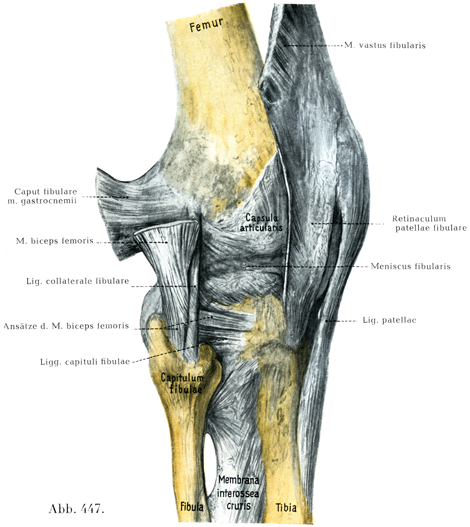

[図447]右の膝関節 外側からみる(3/4)

2. ,3. 脛側および腓側膝蓋支帯Retinacula patellae tibiale, fibulare(図446, 447)は膝蓋骨および膝蓋靱帯に平行して走っている.

両支帯は大腿四頭筋の腱および膝蓋骨の底から起り,解剖のさいは大腿筋膜から多少とも容易に分離することができる.腓側膝蓋支帯は腸脛靱帯Tractus iliotibialisにつづいていて腸脛靱帯粗面Tuberositas tractus iliotibialisに付く.内側膝蓋支帯も脛骨につく.

5. 腓側側副靱帯lig. collaterale fibulareは人体で最も独立性をもった側副靱帯といえるであろう.

大腿骨の外側上顆から起り,腓骨小頭の外側縁につく.長さは5~7cm,太さは約6mmである.この靱帯と関節包とのあいだには,脂肪をふくむ疎性結合組織がある,この靱帯の上部の内側には膝窩筋の腱があり,下部の内外両側には大腿二頭筋の停止束が走っている(図447, 451).